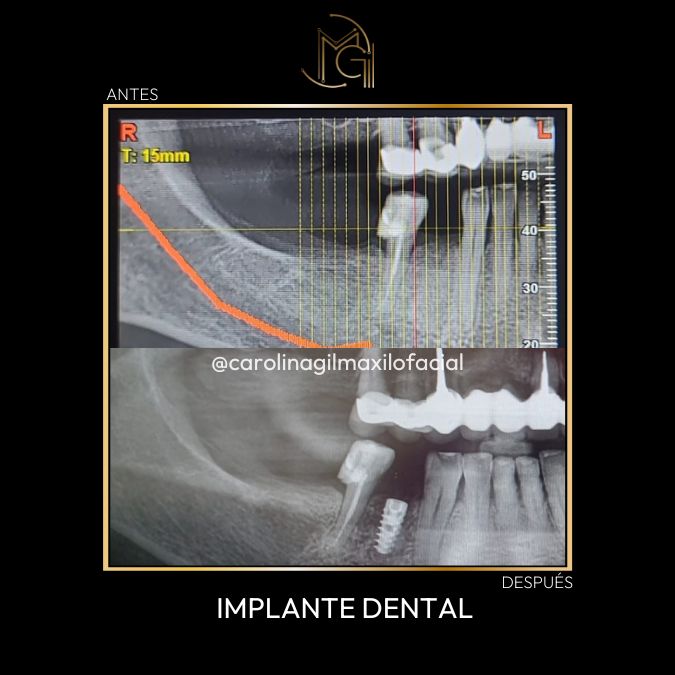

Cirugía Maxilofacial Antes y Después

En nuestro consultorio, la transformación de nuestros pacientes es evidente y significativa. Antes de estos procedimientos, muchos de nuestros pacientes sufrían de dolor crónico, problemas estéticos y dificultades funcionales que afectaban su día a día.

Después de la intervención con la Dra. Carolina Gil, los resultados son impresionantes: una sonrisa renovada, alivio del dolor y una mejora considerable en la funcionalidad oral. Estos cambios no solo impactan la salud física, sino también la autoestima y confianza de nuestros pacientes.

No te pierdas ninguno de nuestros casos de cirugía maxilofacial antes y después.